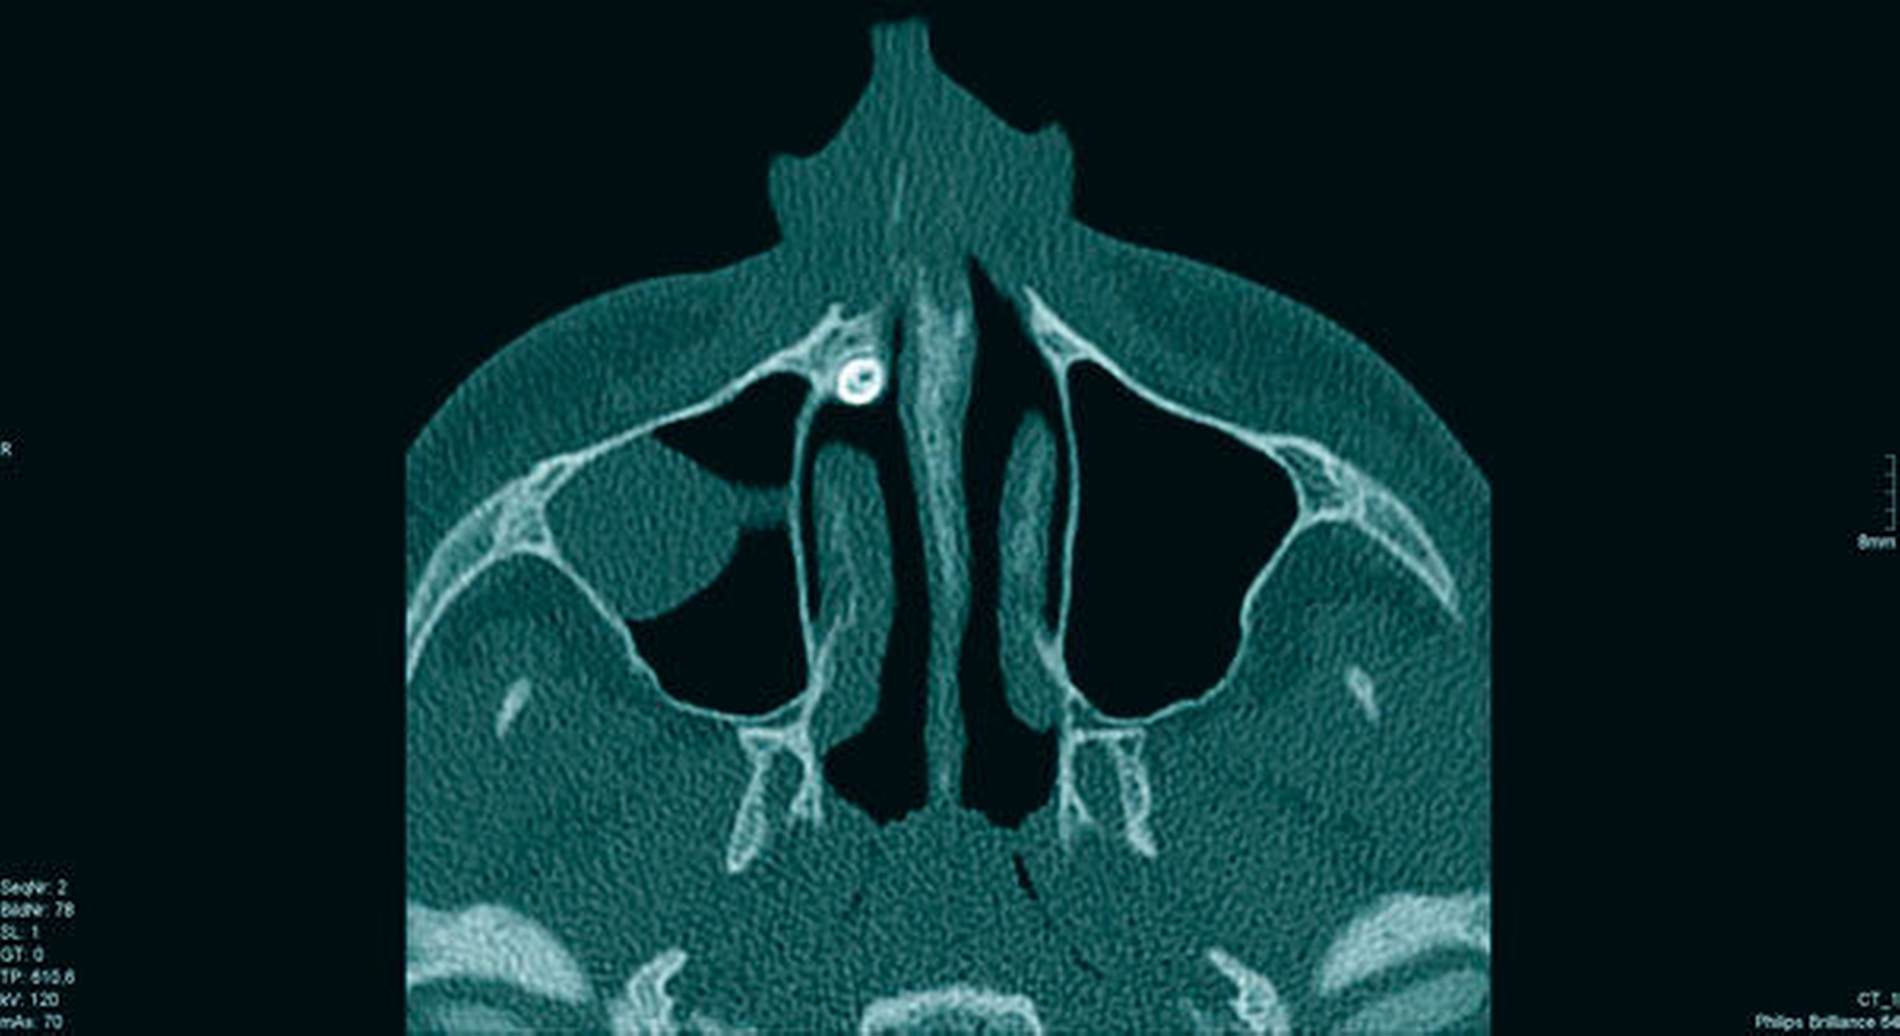

Das angefertigte OPT (Abbildung 1) zeigte einen ektopen, überzähligen Zahn 13a. Nach Komplettierung der Bildgebung durch eine Computertomografie (Abbildungen 2a und 2b) fand sich der Zahn kranial im rechten Nasenboden gelegen. Nebenbefundlich konnte eine polypöse Schleimhautschwellung der rechten Kieferhöhle festgestellt werden.